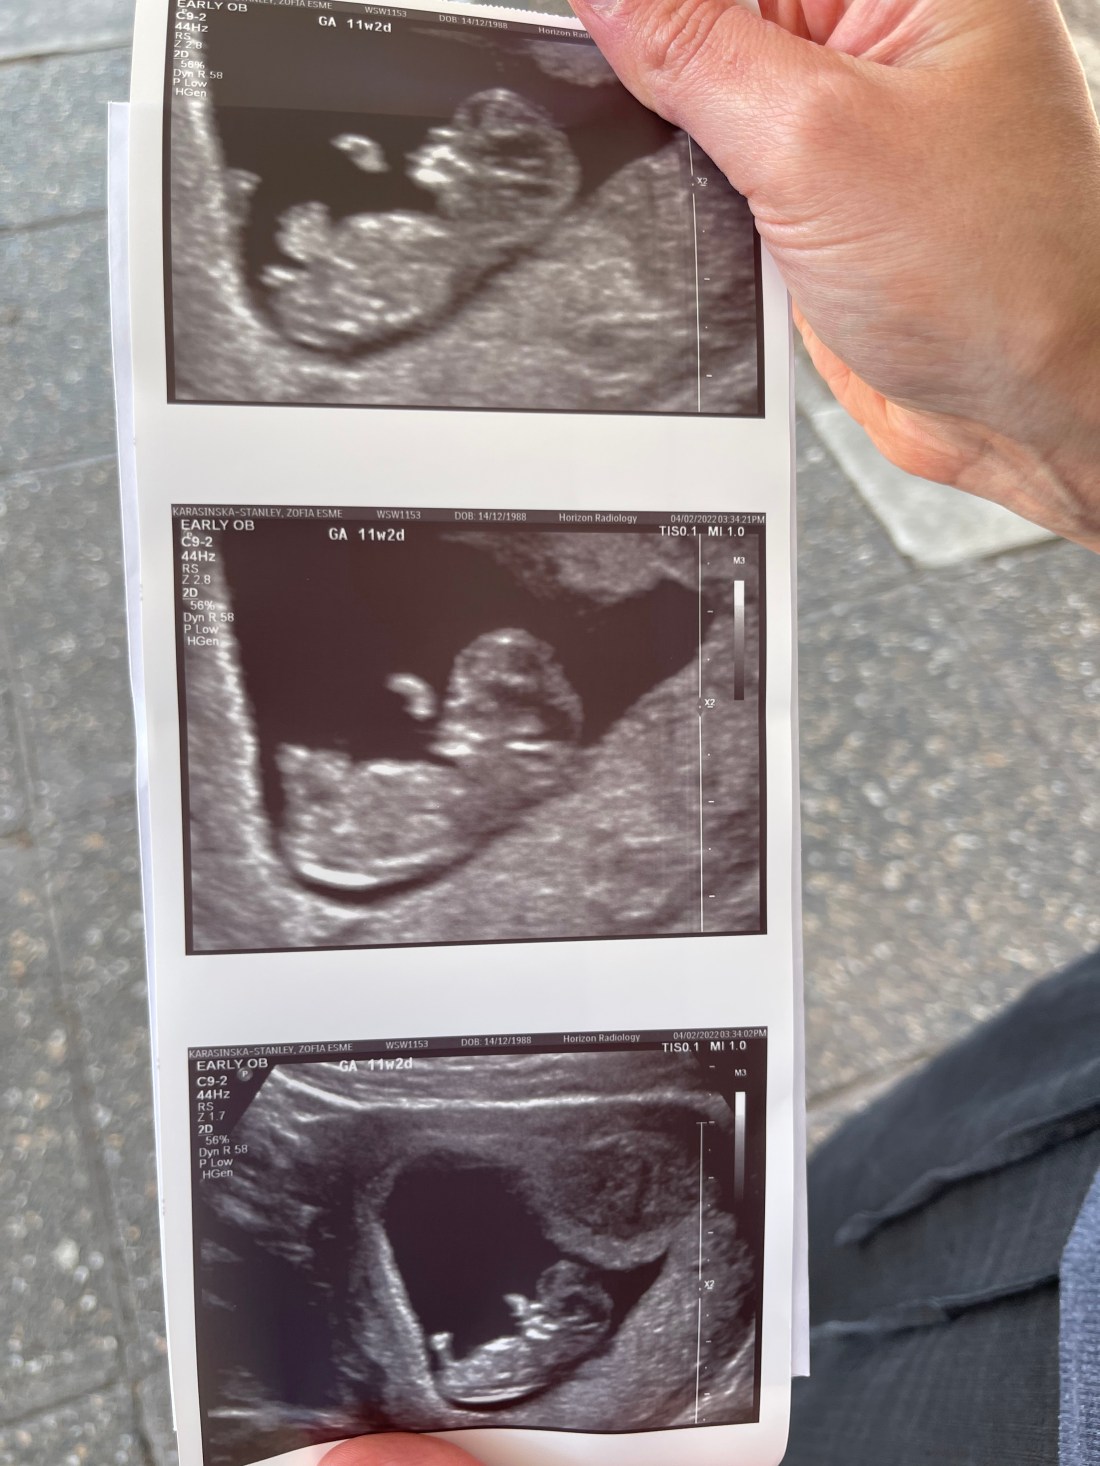

It’s September 1st, 2022. A good ten months since my last post on this site. Tomorrow our baby is due, although it shows no signs of coming yet. And so we wait.

I don’t know if this is a “comeback” post. I have been writing elsewhere, in other forms, and currently I am deep into a really exciting project that takes up most of my writing brain. I’m not sure what lies ahead for this lil blog. But for now let’s put that aside. My freezer is full to bursting, the house never more clean, our baby’s tiny wardrobe washed and folded and tucked away under the cot. My sister and her boyfriend have arrived from the UK on a year-long working holiday visa. After an initial flurry of activity setting them up and showing them around, any reserve of energy I had left feels spent. The past few days have been languid and slow, broken up by wandering from room to room under the reproachful gaze of the dog, who keeps up a constant mournful monologue and keeps peeking his head into cupboards and around doorways, quite sure we are hiding something from him. This evening my body is heavy and tired, my little baby constantly rummaging and poking at the confines of my belly, pushing stretching prodding me as though I were a ball of pizza dough, hooking its foot under my ribs, hiccuping in my pelvis, straining against my bladder and bowel. I place my hand over the bulge in my tummy that will soon be my child, feel it stir and settle underneath. It’s strange to think that from one moment to the next these sensations will all be gone.

There should be a word for this time: the inbetween time, the waiting. It is a strange, restless space, and I wish in my culture there were some ritual, something to guide us over the threshold from one world to the next. I’m excited, and scared, energised, and exhaused. Sometimes I catch myself clenching my fist or jaw, tension in my body somehow disconnected from any conscious thought. If not distracted in coversation or engaged in a task, my brain darts rapidly from one thought to the next: one moment deep into the future, the next years ago in the past. Anywhere but the present. Over the past decade, through medical school and training, I have become so accustomed to making the most of any free window of time that my brain now seems irreversibly programed to offer me every possible way in which I could fill it, conditioned to look for the best possible way to multitask in order to achieve maximum gain. It’s actually – always – very calming just to pause and write.